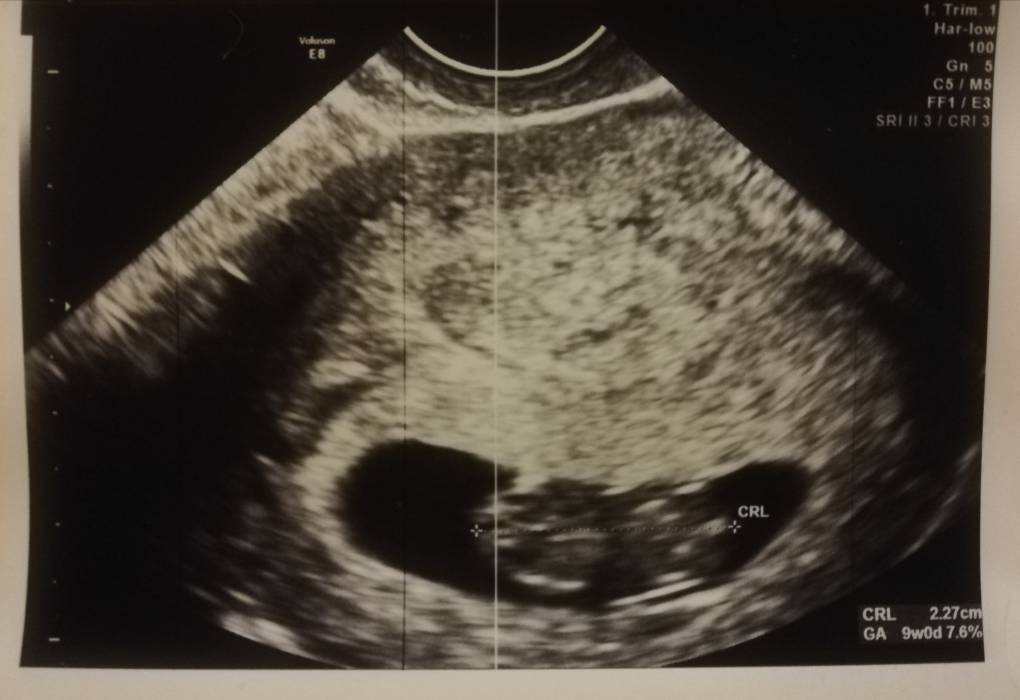

Ale pomijając cała wizytę martwi mnie kształt pęcherzyka... Nie jest taki ładny, okrągły jak u Was, tylko jakiś taki podłużny, mam wrażenie że mało tam miejsca? Lekarz niby powiedział, że nie ma to wpływu, że dużo kobiet tak ma, ale szczerze to w ogóle mu nie ufam i się martwię.. [emoji24][emoji24] Maluszek ma już 2,27cm, więc rośnie ładnie (ostatnio w 6t2d było 0,53cm), ale np pęcherzyk żółtkowy bez zmian - 45mm. Proszę, powiedzcie mi czy to normalne bo zaczynam wariowac i co z tym pęcherzykiem [emoji24][emoji24] miałam jutro powiedzieć w pracy o ciąży ale teraz jestem jeszcze bardziej przerażona czy wszystko jest w porządku.. [emoji27] Błagam o jakieś podpowiedzi [emoji24]Zobacz załącznik 1232113